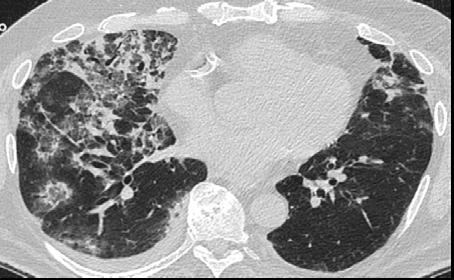

A 58-year-old female with recently diagnosed COVID-19 pneumonia was found to have a dry cough and dyspnoea in the setting of persistent bilateral hilar and mediastinal lymphadenopathy associated with bilateral nodular infiltrates. Of note, she immigrated to the USA from India 10 years prior, with the most recent travel to India 2 years ago. Quantiferon testing upon return to the USA was negative at that time. Workup included bronchoscopy with endobronchial ultrasound revealing non-caseating granulomas with negative stains for acid-fast bacilli (AFB). She was diagnosed with Stage 3 sarcoidosis and initiated on prolonged steroid taper with improvement of symptoms. With taper of steroid dose, however, she developed lymphocyte-predominant exudative effusion with negative cultures, and was reinitiated on a protracted steroid course with rapid symptom resolution. At 4-month follow-up, she had worsening CT findings upon steroid taper, and was started on azathioprine. One month later, she required hospital admission for worsening dyspnoea and fatigue. She was noted to be febrile, tachycardic, and tachypnoeic with worsening

hypoxia. Subsequent CT chest showed progression of bilateral nodular infiltrates with new right upper lobe consolidation and air bronchograms concerning for multifocal pneumonia (Figure 1). Incidentally, she was also noted to have calcified splenic granulomas. She developed rapid clinical deterioration, ultimately requiring mechanical ventilation, pressor support, and continuous renal replacement therapy. Repeat bronchoscopy revealed diffuse alveolar haemorrhage with multiple AFB smears positive for Mycobacterium tuberculosis. She was immediately initiated on quadruple therapy, but unfortunately, despite treatment, developed refractory shock and passed away 2 weeks after initial presentation.

A) Initial adenopathy with peripheral patchy ground glass opacities in the right lung following COVID-19 pneumonia. B) Persistent bulky adenopathy 1 year after initial presentation. C) Extensive nodularity throughout the right lung with increasing confluent opacities in the right upper lobe and stable mediastinal lymphadenopathy 2 years after initial presentation. D) Tuberculosis superimposed on sarcoidosis with progression of nodular infiltrates, worsening right upper lobe consolidation, and air bronchograms with incidental calcified splenic granulomas (not pictured).

Figure 1: CT progression of patient’s sarcoidosis and tuberculosis.